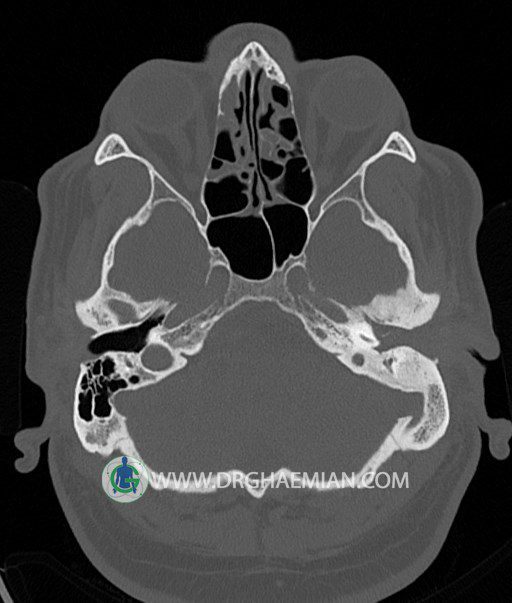

سی تی اسکن گوش داخلی به رادیولوژیست اجازه می دهد تا سطوح مختلف، یا اسلایس هایی از استخوان های که از جمجه به گوش می روند را از طریق امواج ایکس چرخشی مشاهده کند. در این کیس اودیت مدیا، ماستوئیدیت مزمن، اوتیت خارجی، انحراف سپتوم بینی، کونکا بولوزا و افزایش ضخامت سینوس ها مشاهده می شود.

در HRCT از استخوان تمپورال با مقاطع آگزيال ، ساژيتال و کرونال ظريف ( 0.6 mm ) :

– نماي کوکلهآي دو طرف با 2.5 دور گردش مجرا

– نماي cochlear aqueduct

– نماي semicircular canal خلفي ، لترال ، فوقاني و وستيبول

– استخوانچه هاي گوش داخلي شامل malleus ، incus و stapes (دنسيتي و رديف استخوانچه ها )

– نماي oval window و round window ، tympanic cavity ، attic و کانال گوش داخلي

– کانال عصب فاشيال و مسير ان از ناحيه کانال گوش داخلي ، geniculate ganglion تا محل خروج ان از stylomastoid foramen

– نماي tympanic membrane ، کانال ICA ، بولب جوگولار دو طرف

در حد طبيعي است .

– اپاسيتي گوش مياني چپ ناشي از وجود دانسيته نسج نرمي دراطراف استخوانچه ها همراه با اروژن اسکوتوم و

استخوانچه ها بدون جابجايي در رديف استخوانچه ها مشهود است که مطرح کننده اوتيت مديا همراه با نشانه

هاي مشکوک به کولستئاتوم مي باشد .

– اپاسيتي و اسکلروزيس ماستوئيد چپ نشانه ماستوئيديت مزمن

– اپاسيتي کانال گوش خارجي ناشي از دانسيتي نسج نرمي مطرح کننده external otitis

– انحراف سپتوم مياني بيني به راست

– کونکا بولوزا در کونکاي مياني چپ و

– افزايش ضخامت مخاطي در سينوس هاي اتموئيد و ماگزيلاري

اپاسيته